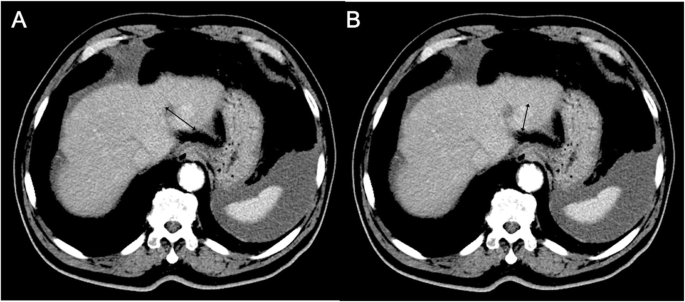

结果解读:WHO标准因“观察者间变异大、无法适配新型成像技术”被RECIST取代;RECIST 1.1虽优化了靶病灶选择与PET的纳入,但仍未解决“功能特征评估”的问题——例如在HCC中,RECIST无法区分“肿瘤坏死”与“活性肿瘤”,需依赖mRECIST(测量动脉期增强的活性病灶,图1)。